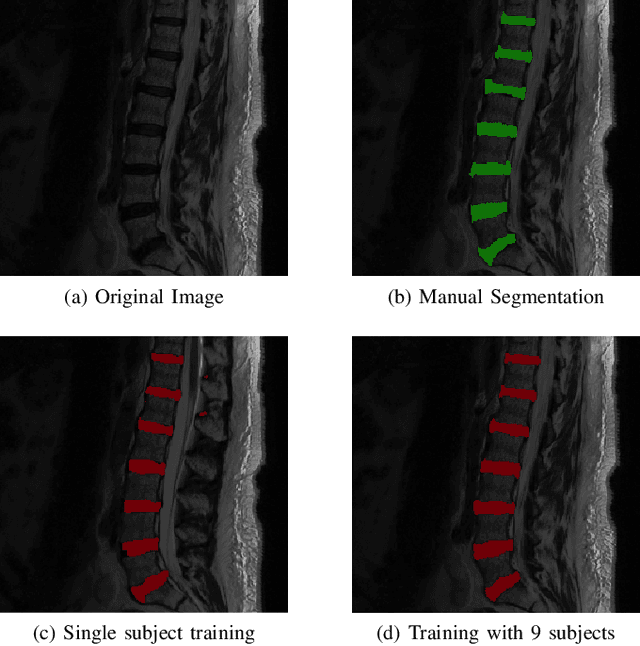

Abstract:Yes, it can. Data augmentation is perhaps the oldest preprocessing step in computer vision literature. Almost every computer vision model trained on imaging data uses some form of augmentation. In this paper, we use the inter-vertebral disk segmentation task alongside a deep residual U-Net as the learning model, to explore the effectiveness of augmentation. In the extreme, we observed that a model trained on patches extracted from just one scan, with each patch augmented 50 times; achieved a Dice score of 0.73 in a validation set of 40 cases. Qualitative evaluation indicated a clinically usable segmentation algorithm, which appropriately segments regions of interest, alongside limited false positive specks. When the initial patches are extracted from nine scans the average Dice coefficient jumps to 0.86 and most of the false positives disappear. While this still falls short of state-of-the-art deep learning based segmentation of discs reported in literature, qualitative examination reveals that it does yield segmentation, which can be amended by expert clinicians with minimal effort to generate additional data for training improved deep models. Extreme augmentation of training data, should thus be construed as a strategy for training deep learning based algorithms, when very little manually annotated data is available to work with. Models trained with extreme augmentation can then be used to accelerate the generation of manually labelled data. Hence, we show that extreme augmentation can be a valuable tool in addressing scaling up small imaging data sets to address medical image segmentation tasks.